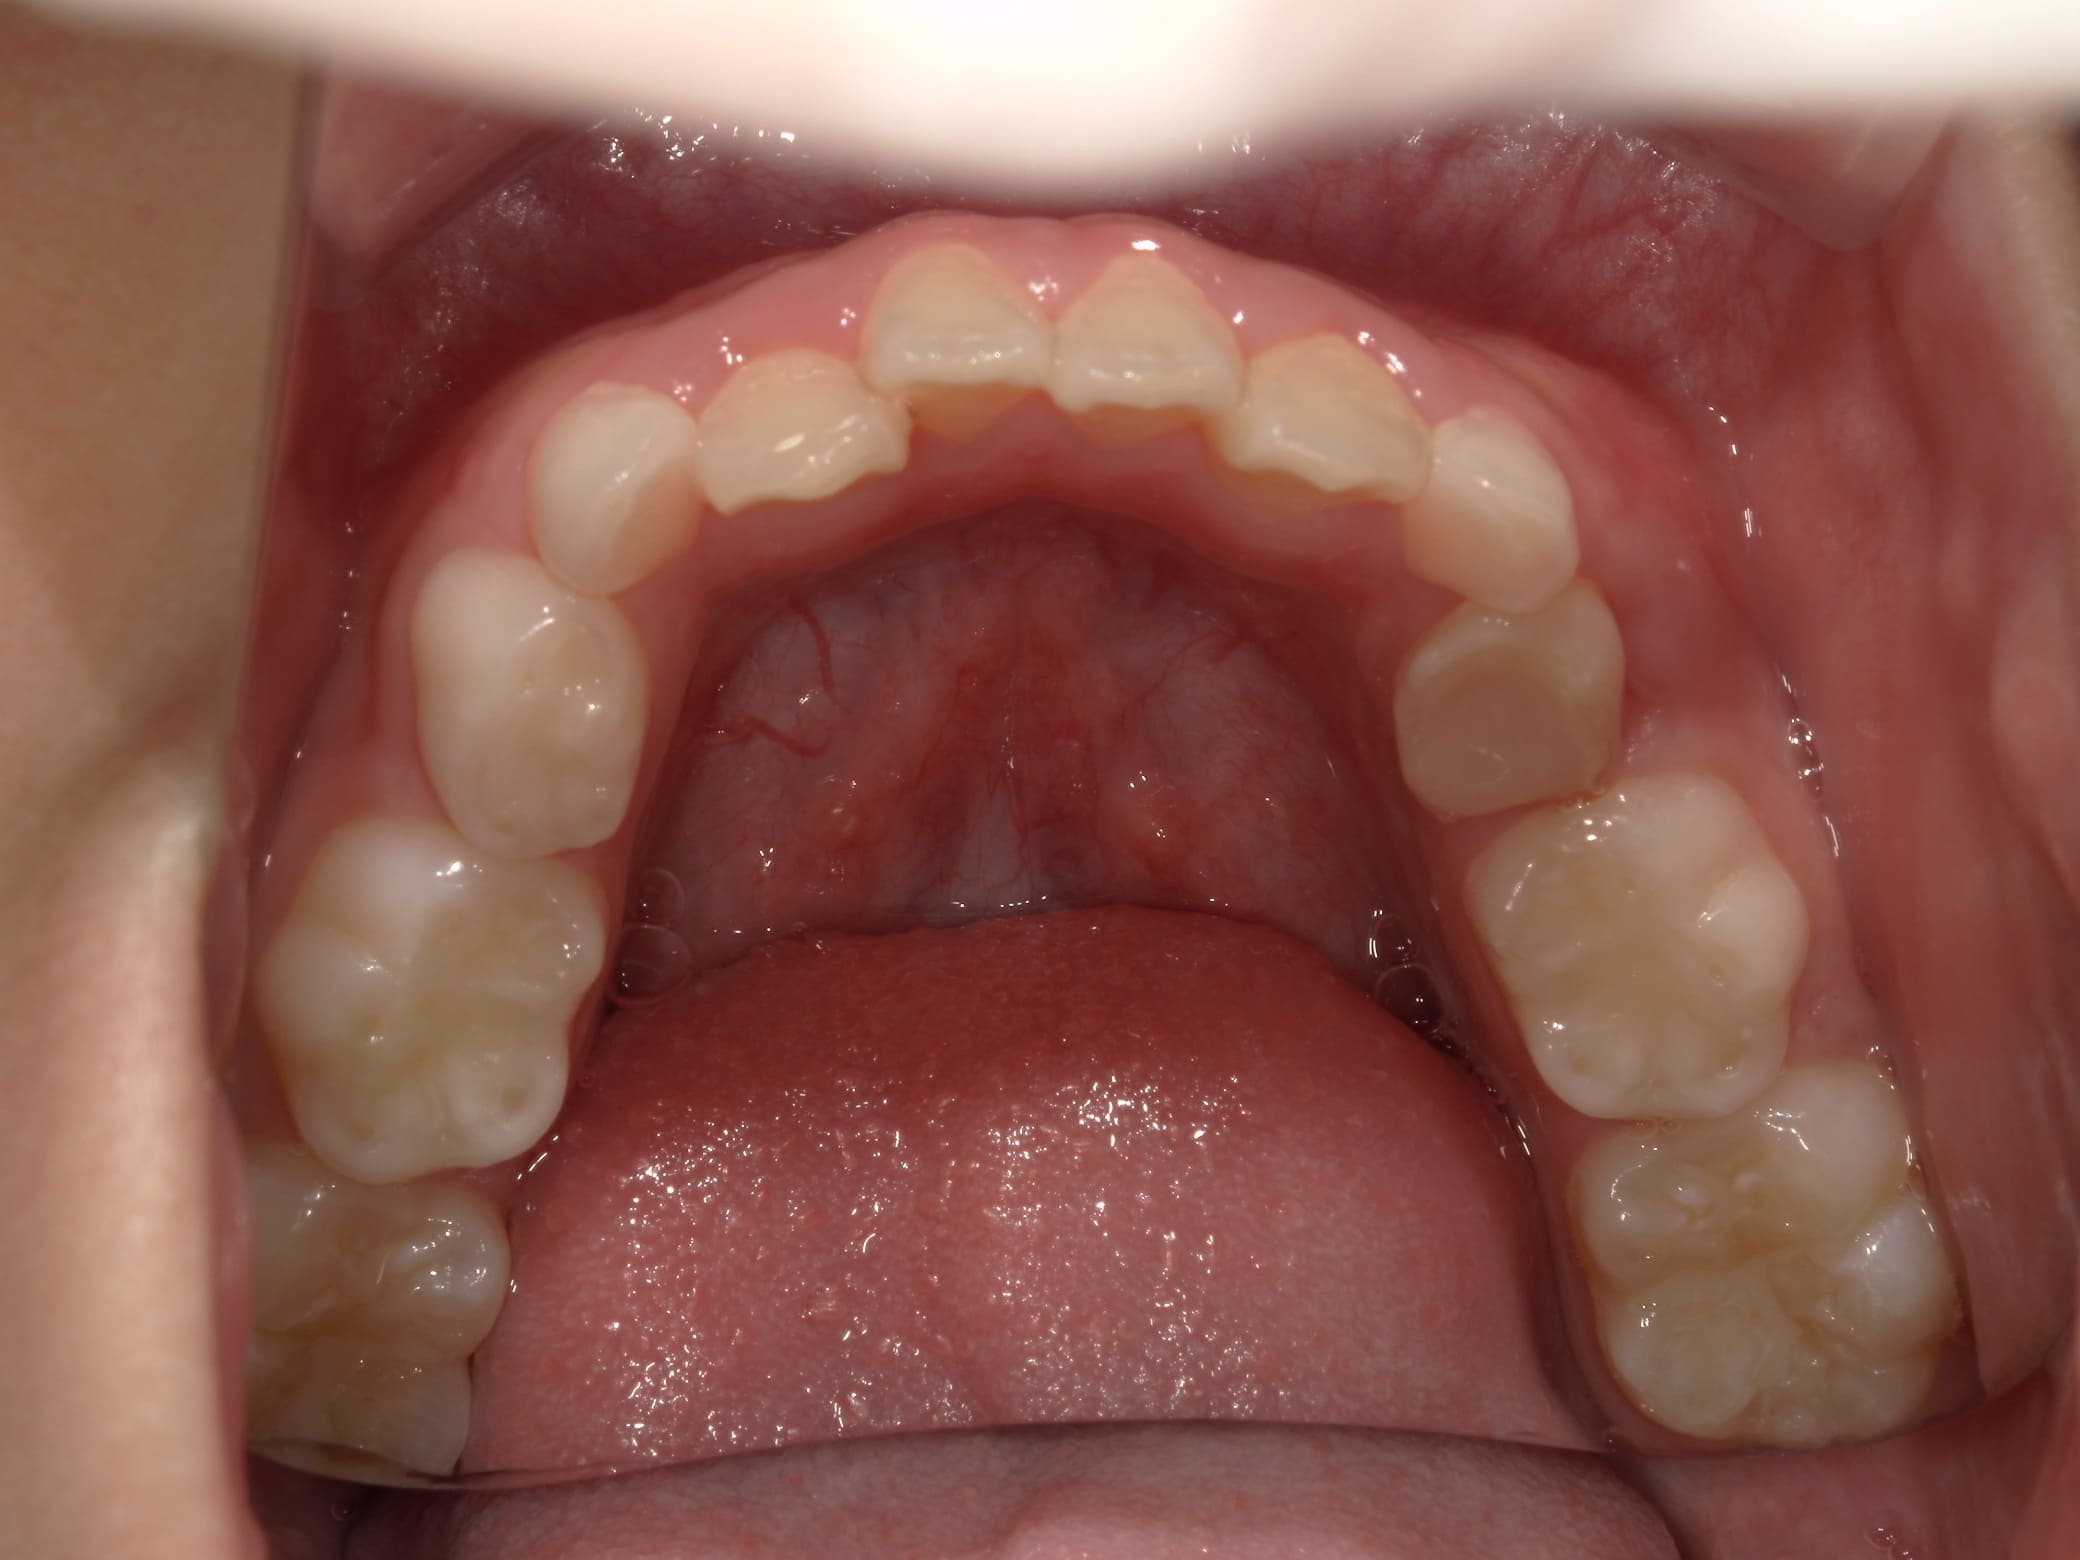

| 年齢・性別 | 8歳3ヶ月の男児 |

|---|---|

| 主訴 | 上顎前歯の位置異常に不安を抱え、歯並びと将来的な咬合状態を整える目的で来院された患者様です。 特に左側の前歯(中切歯および側切歯)の萌出が確認できないことがきっかけとなりました。 |

| 治療期間・回数 | 約5年10ヶ月 |

| 費用 | 460,000円(税別) |